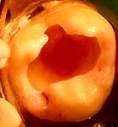

En 2013 concurre paciente de sexo femenino de 37 años de edad a la Clínica Integrada II UdelaR por caries profunda en pieza 37 (Fig. 2a). Se diagnostica CPPA ya que solo el test de fresado da positivo. Se planifica eliminación total de caries de paredes laterales con aislación absoluta. Se observa último test colorimétrico con rojo ácido 52 en propilenglicol (Detector, Pharma Dent, Uruguay) dejando fina capa de dentina infectada en pared axial (Fig. 2b) la cual se protege con mezcla de hidróxido de calcio (Ca(OH)2) puro con suero fisiológico y luego encima Ca(OH)2 fraguable (Life, Kerr, USA) (Fig. 2c). Se sella con ionómero vítreo (Gold Label Luting & Lining Cement, Tokyo, Japan).